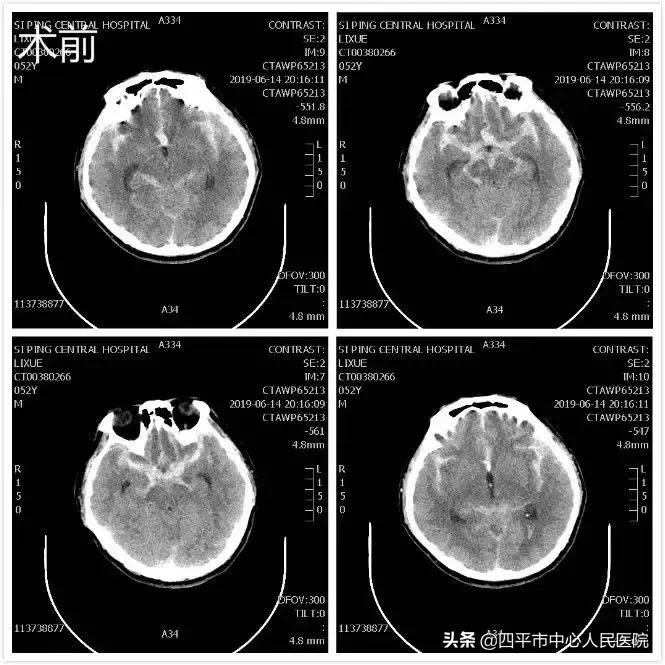

Case 5 左侧脑出血,发现左侧后交通动脉未破裂动脉瘤

患者孙XX,入院前约21小时无明显诱因突发言语不清伴右侧肢体活动不灵,表现为肢体瘫痪,既往高血压病史约10年,最高可达180mmHg,不规律服用降压药物急被家属送至我院就诊,急送我院急诊给予查头部CT后,示脑出血。患者入院后病情呈进行性加重,患者符合手术指征,行头部CT定位见出血量增加,头部CTA示相当于左侧后交通动脉起始部小动脉瘤,李晓东主任带领马龙医生在清除脑出血的同时将动脉瘤夹闭,出院时,患者病情平稳,预后较好。